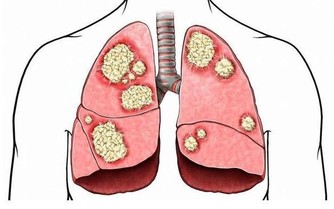

三、消化功能減弱

早期患者會感覺到腹部脹痛,而且不願意吃東西,伴有消化不良現象。這種情況不是持續性的,偶爾會感覺到胃脹,後來會有所緩解。嚴重的患者有可能出現腸梗阻,會出現陣發性的腹部疼痛,糞便帶血現象。

在按壓腹部時,患者會明顯的感覺疼痛,而且也會有包塊的存在。這是腫瘤跟周圍的組織粘在一起形成的腫塊,而且這些腫塊會活動。在檢查B超時,會發現腫塊的大小不規則,尤其是到了晚期,腫塊會不斷增大,變得不再活動。